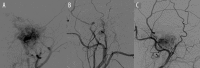

Case report: We report the endovascular approach to three patients harboring glomus jugulare paragangliomas. In all cases incomplete occlusion of the lesions was achieved and recanalization in the follow-up period was revealed. Two patients presented no clinical improvement and the remaining one experienced a transient withdrawal of tinnitus.

Conclusions: It is technically difficult to achieve complete obliteration of glomus jugulare tumors with the use of embolization and the subtotal occlusion poses a high risk of revascularization and is not beneficial in terms of alleviating clinical symptoms.